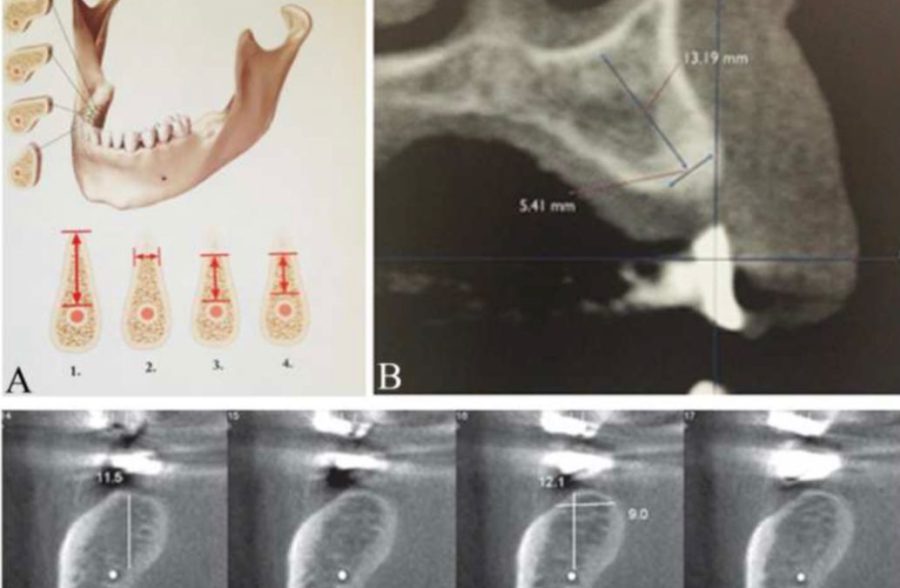

Different methods to evaluate mandibular alveolar ridge in Cone Beam Computed Tomography images in pre-implant surgery assessments